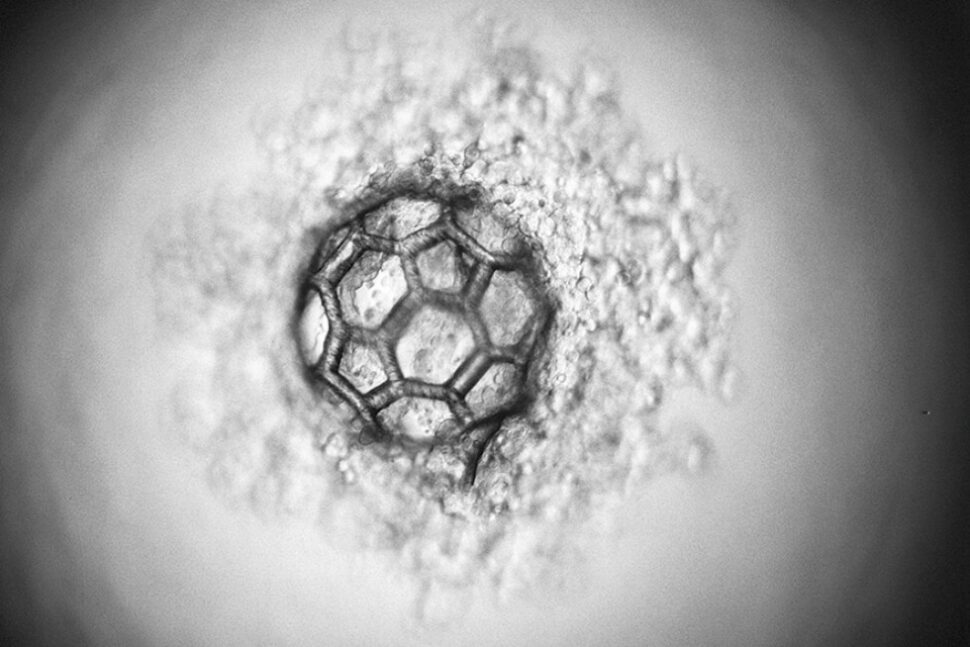

Biokompatible Mikrofasern als Gerüst für Organe effizient hergestellt

Wer Haut und Organe per Tissue Engineering herstellen möchte, benötigt körperverträgliche Mikrofasern als Gerüst. Daran forscht ein Team der TU Graz.